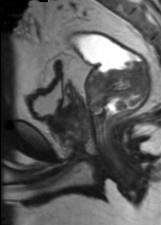

问题 男,70岁,下腹部腹胀、腹痛、排便困难,逐渐加重,MRI示直肠内不规则充盈缺损,请选择最佳诊断结果()

选项 A.直肠息肉 B.直肠癌 C.直肠间质瘤 D.直肠转移瘤 E.直肠淋巴瘤

答案 B